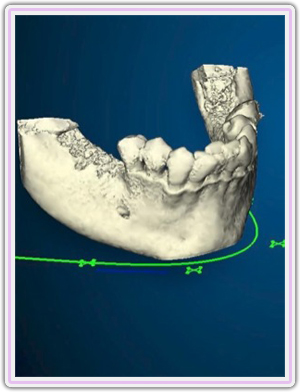

3d Positioning Of The Implant On The Lower Jaw